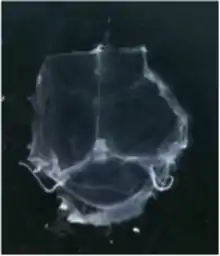

To visualize the dura mater using immunohistochemistry, the dura must first be fixed within the skullcap. It is prepared by cutting around the base of the skull (inferior to the post-tympanic hook) and removing the lower portion of the skull and brain. Following fixation, the dura can be dissected out of the skullcap as a single piece of tissue that can be utilized for histological analysis.[13]

In transgenic mice containing Prox1-GFP or Vegfr3-LacZ reporter genes, the lymphatic vessels may be visualized by fluorescent microscopy or after X-gal staining, respectively.[2]